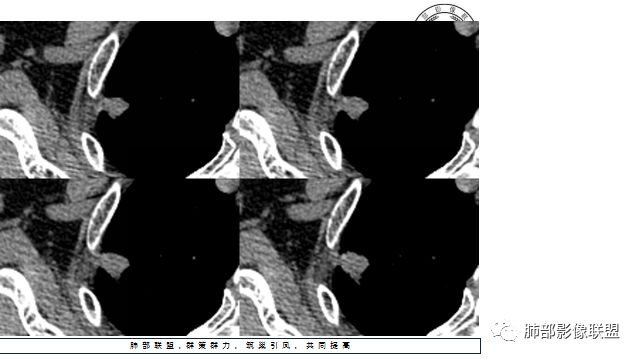

4.增强扫描成明显环形强化,中央液化坏死,内壁清楚且较为规整。

分析:

1.肺鳞癌是容易坏死,但如此小的结节出现影像明显可见的坏死区,且内壁如此清楚规整,我们临床实践中肿瘤非常少见,重要的事情说三遍!!!